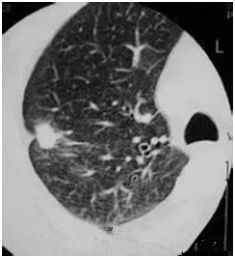

●高危結(jié)節(jié)

●結(jié)節(jié)呈毛栗子樣,周圍有角(棘突)和細(xì)小毛刺生長

●結(jié)節(jié)如月亮,周圍有一圈暈

●結(jié)節(jié)呈分葉狀

●多位于上葉結(jié)節(jié)

●結(jié)節(jié)里有較粗的血管牽扯進(jìn)來

●結(jié)節(jié)里有透亮的小空泡(空氣支氣管征)

●結(jié)節(jié)外圍有胸膜牽拉征象(臍凹征)

●隨訪3—6月以上,結(jié)節(jié)明顯增大或內(nèi)部密度增高